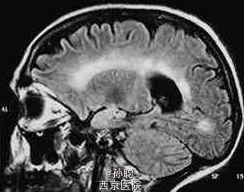

患者女性,31岁,教师,因有房屋旋转感和行走不稳2天就诊。房屋旋转感呈持续性,平卧时可部分缓解。这些症状使患者无法正常工作。发病无明显诱因,无其他不适,无恶心和头痛。自觉听力正常,无耳鸣。无其他神经系统症状的主诉。目前仅服用口服避孕药。患者在3个月前度假时用左眼照相有困难。该症状在1周内自发缓解,患者未寻找原因。最近,尤其是在穿衣服时右手发生轻度震颤,但由于患者是左利手,故未造成大碍。 体格检查:一般情况可。无发热,心血管检查正常。视诊耳道和鼓膜无异常,临床检测无听力受损表现。右眼视力6/6,左眼视力6/9。双侧瞳孔对称,左眼瞳孔传入缺陷。眼底镜检查示左眼视盘较右眼苍白。眼外肌运动检查发现,当看向右侧和垂直凝视时出现眼球震颤。眼球震颤与头位无关且不易疲劳。其他颅神经检查正常。肌力、肌张力和肢体反射均正常。但指鼻试验示右上肢呈意向性震颤,右手快速轮替运动较左手差。其他协调功能和感觉功能正常。 脑脊液(CSF)检查发现,CSF中IgG水平升高,IgG在电泳中分解成寡克隆带。脑脊液检查显示单核细胞计数和蛋白质中度升高,寡克隆带阳性。